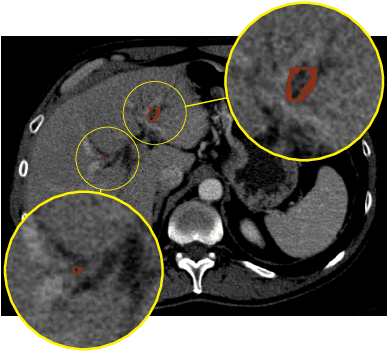

Automatic liver lesion segmentation is a challenging task while having a significant impact on assisting medical professionals in the designing of effective treatment and planning proper care. In this paper we propose a cascaded system that combines both 2D and 3D convolutional neural networks to effectively segment hepatic lesions. Our 2D network operates on a slice by slice basis to segment the liver and larger tumors, while we use a 3D network to detect small lesions that are often missed in a 2D segmentation design. We employ this algorithm on the LiTS challenge obtaining a Dice score per case of 68.1%, which performs the best among all non pre-trained models and the second best among published methods. We also perform two-fold cross-validation to reveal the over- and under-segmentation issues in the LiTS annotations.